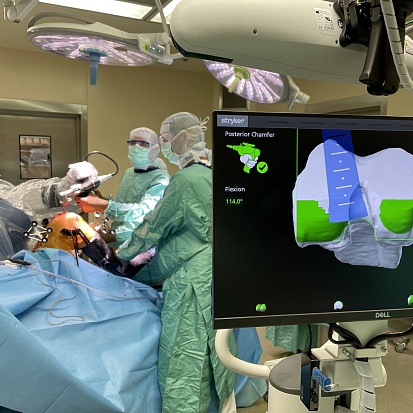

Федеральный центр травматологии, ортопедии и эндопротезирования продолжает ...

Роботизированные технологии в Федеральном центре